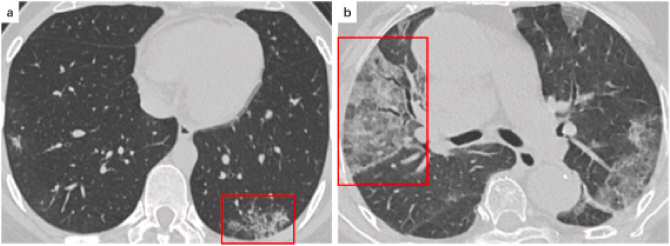

TomografÃas axiales computerizadas de tórax con lesiones causadas por la COVID-19. (Imágenes: UB)

El algoritmo se ha probado con 79 volúmenes y 110 secciones de TAC en los que se habÃa detectado infección por SARS-CoV-2, obtenidos en tres repositorios de imágenes de acceso libre. De media, se consiguió una precisión para la segmentación de lesiones causadas por el virus de casi el 99%, y no se observó ningún falso positivo durante la identificación.

En concreto, el funcionamiento del sistema consiste en «una primera fase de segmentación de los pulmones a partir de la imagen TAC para reducir el área de búsqueda», explica Pezzano. «Posteriormente, se utiliza un algoritmo para analizar el área de los pulmones y detectar la presencia de la COVID-19. En caso de resultado positivo, la imagen se procesa para identificar las áreas afectadas por la enfermedad», añade.